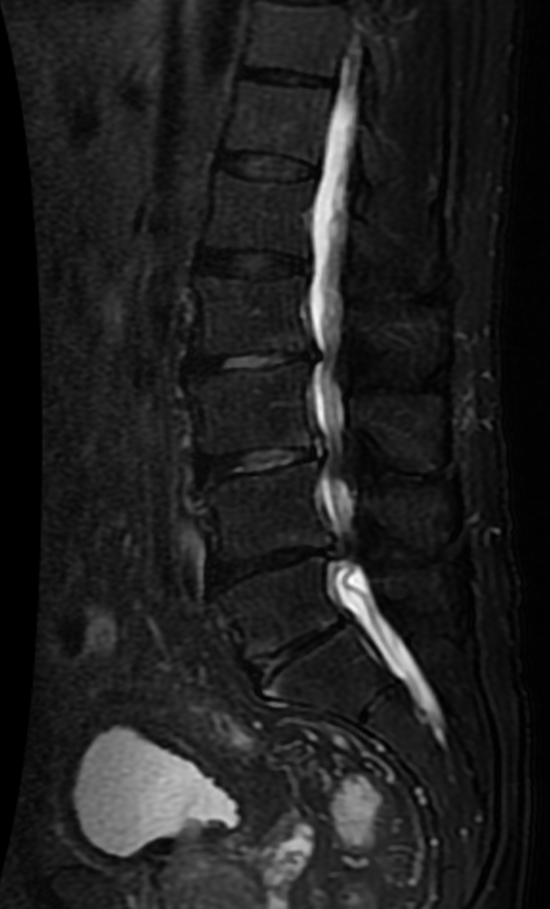

Normal lumbar spine phantom with healthy vertebral bodies, intact discs, spinal canal, and nerve roots

L4-L5 posterolateral disc herniation compressing the L5 nerve root with disc desiccation, annular tear, and...

Lumbar spinal stenosis with ligamentum flavum hypertrophy, facet joint arthropathy, disc bulge, and narrowed central canal